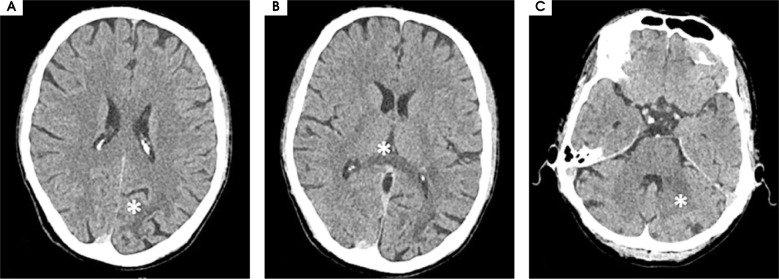

Purpose: Progressive multifocal leukoencephalopathy (PML) is a lethal demyelinating disease of the central nervous system caused by John Cunningham virus (JCV). PML develops due to the reactivation of latent JCV infection in individuals with cellular immunodeficiency. Since the beginning of acquired immunodeficiency syndrome (AIDS) epidemic, human immunodeficiency virus (HIV) infection has remained a leading cause of PML with the condition recognized as an AIDS-defining illness. The clinical manifestations of PML may vary depending on the underlying condition. In AIDS-associated PML, the symptoms include motor weakness, speech or language disturbances, cognitive and behavioral changes and gait abnormalities and incoordination.

Case description: We present the case of a male patient who developed PML as the first clinical manifestation of a newly diagnosed HIV infection.